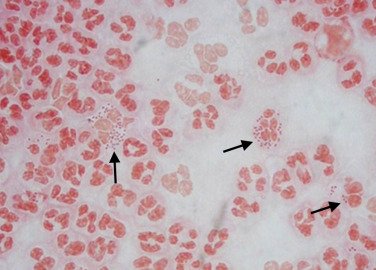

⭕ العينه تكون شفافه، اي لون يظهر او عدم وضوح العينه(عكاره).. تعتبر العينه غير طبيعيه.

?لون احمر او وردي يعني وجود دم في العينه ?